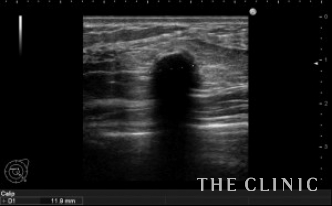

しこりの位置と、エコー所見です。

左は11.8mm と6.1mm